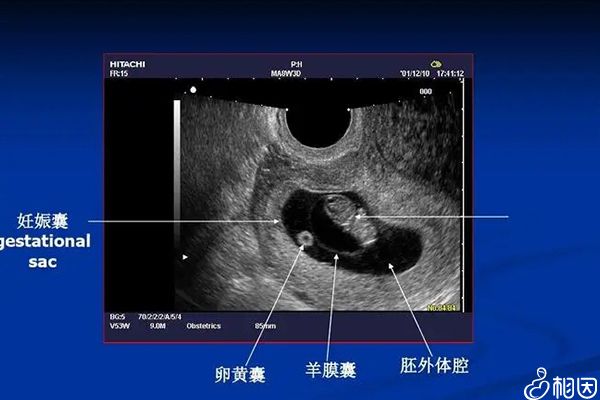

并且需要注意的是,计算出的怀孕天数或多或少也有一定的误差,建议最好以实际为准。一般移植胚胎后看胚胎发育情况,绝大多数囊胚移植胚胎后,三周在宫腔内就可以看到妊娠囊。

在移植囊胚时,一般会通过B超检查子宫内膜的厚度,并结合平时月经周期,择在排卵期时移植。这样不仅能增大移植成功的可能性,还能在一定程度上减小囊胚移植宫外孕几率,降低手术对女性伤害。